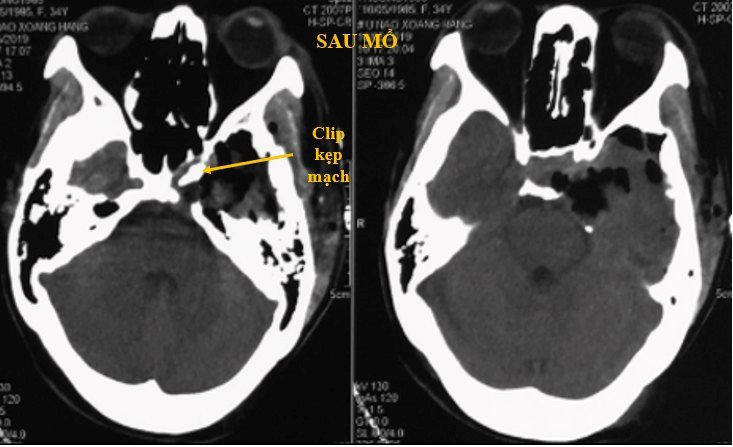

Bệnh nhân được phẫu thuật lấy gần toàn bộ u, xét nghiệm là u mạch thể hang. Sau mổ bệnh nhân có liệt tạm thời dây thần kinh III trái, hồi phục hoàn toàn sau 3 tháng, chỉ còn tê bì vùng mặt hàm trên bên trái.

Theo dõi sau 2 năm, bệnh nhân ổn định, khối u gần như không còn trên phim cộng hưởng từ.